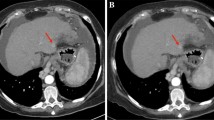

The image noise and beam-hardening artefact decreased significantly as the iDose level increased (p < 0.05). However, the scores for subjective image quality, such as the visibility of small intrahepatic vascular structures, lesion conspicuity, and overall image quality were highest with iDose level 4 (Fig. 1). Both observers complained of the artificial, plastic look of the images at iDose level 5 or 6 (Fig. 2). Interobserver agreement for the qualitative analysis was moderate to almost perfect (Table 1).

Axial contrast-enhanced multidetector CT images in a 60-year-old man with a history of subtotal gastrectomy due to gastric cancer. Images obtained during the portal phase with a FBP, b iDose level 2, c iDose level 4, d iDose level 6 shows gradually reduced image noise with increasing iDose level. However, due to excessive noise reduction in iDose level 6 image, both observers complained of “plastic” appearance of the image